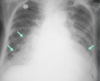

What are the four arrows pointing at?

* Cavitary Infiltrate